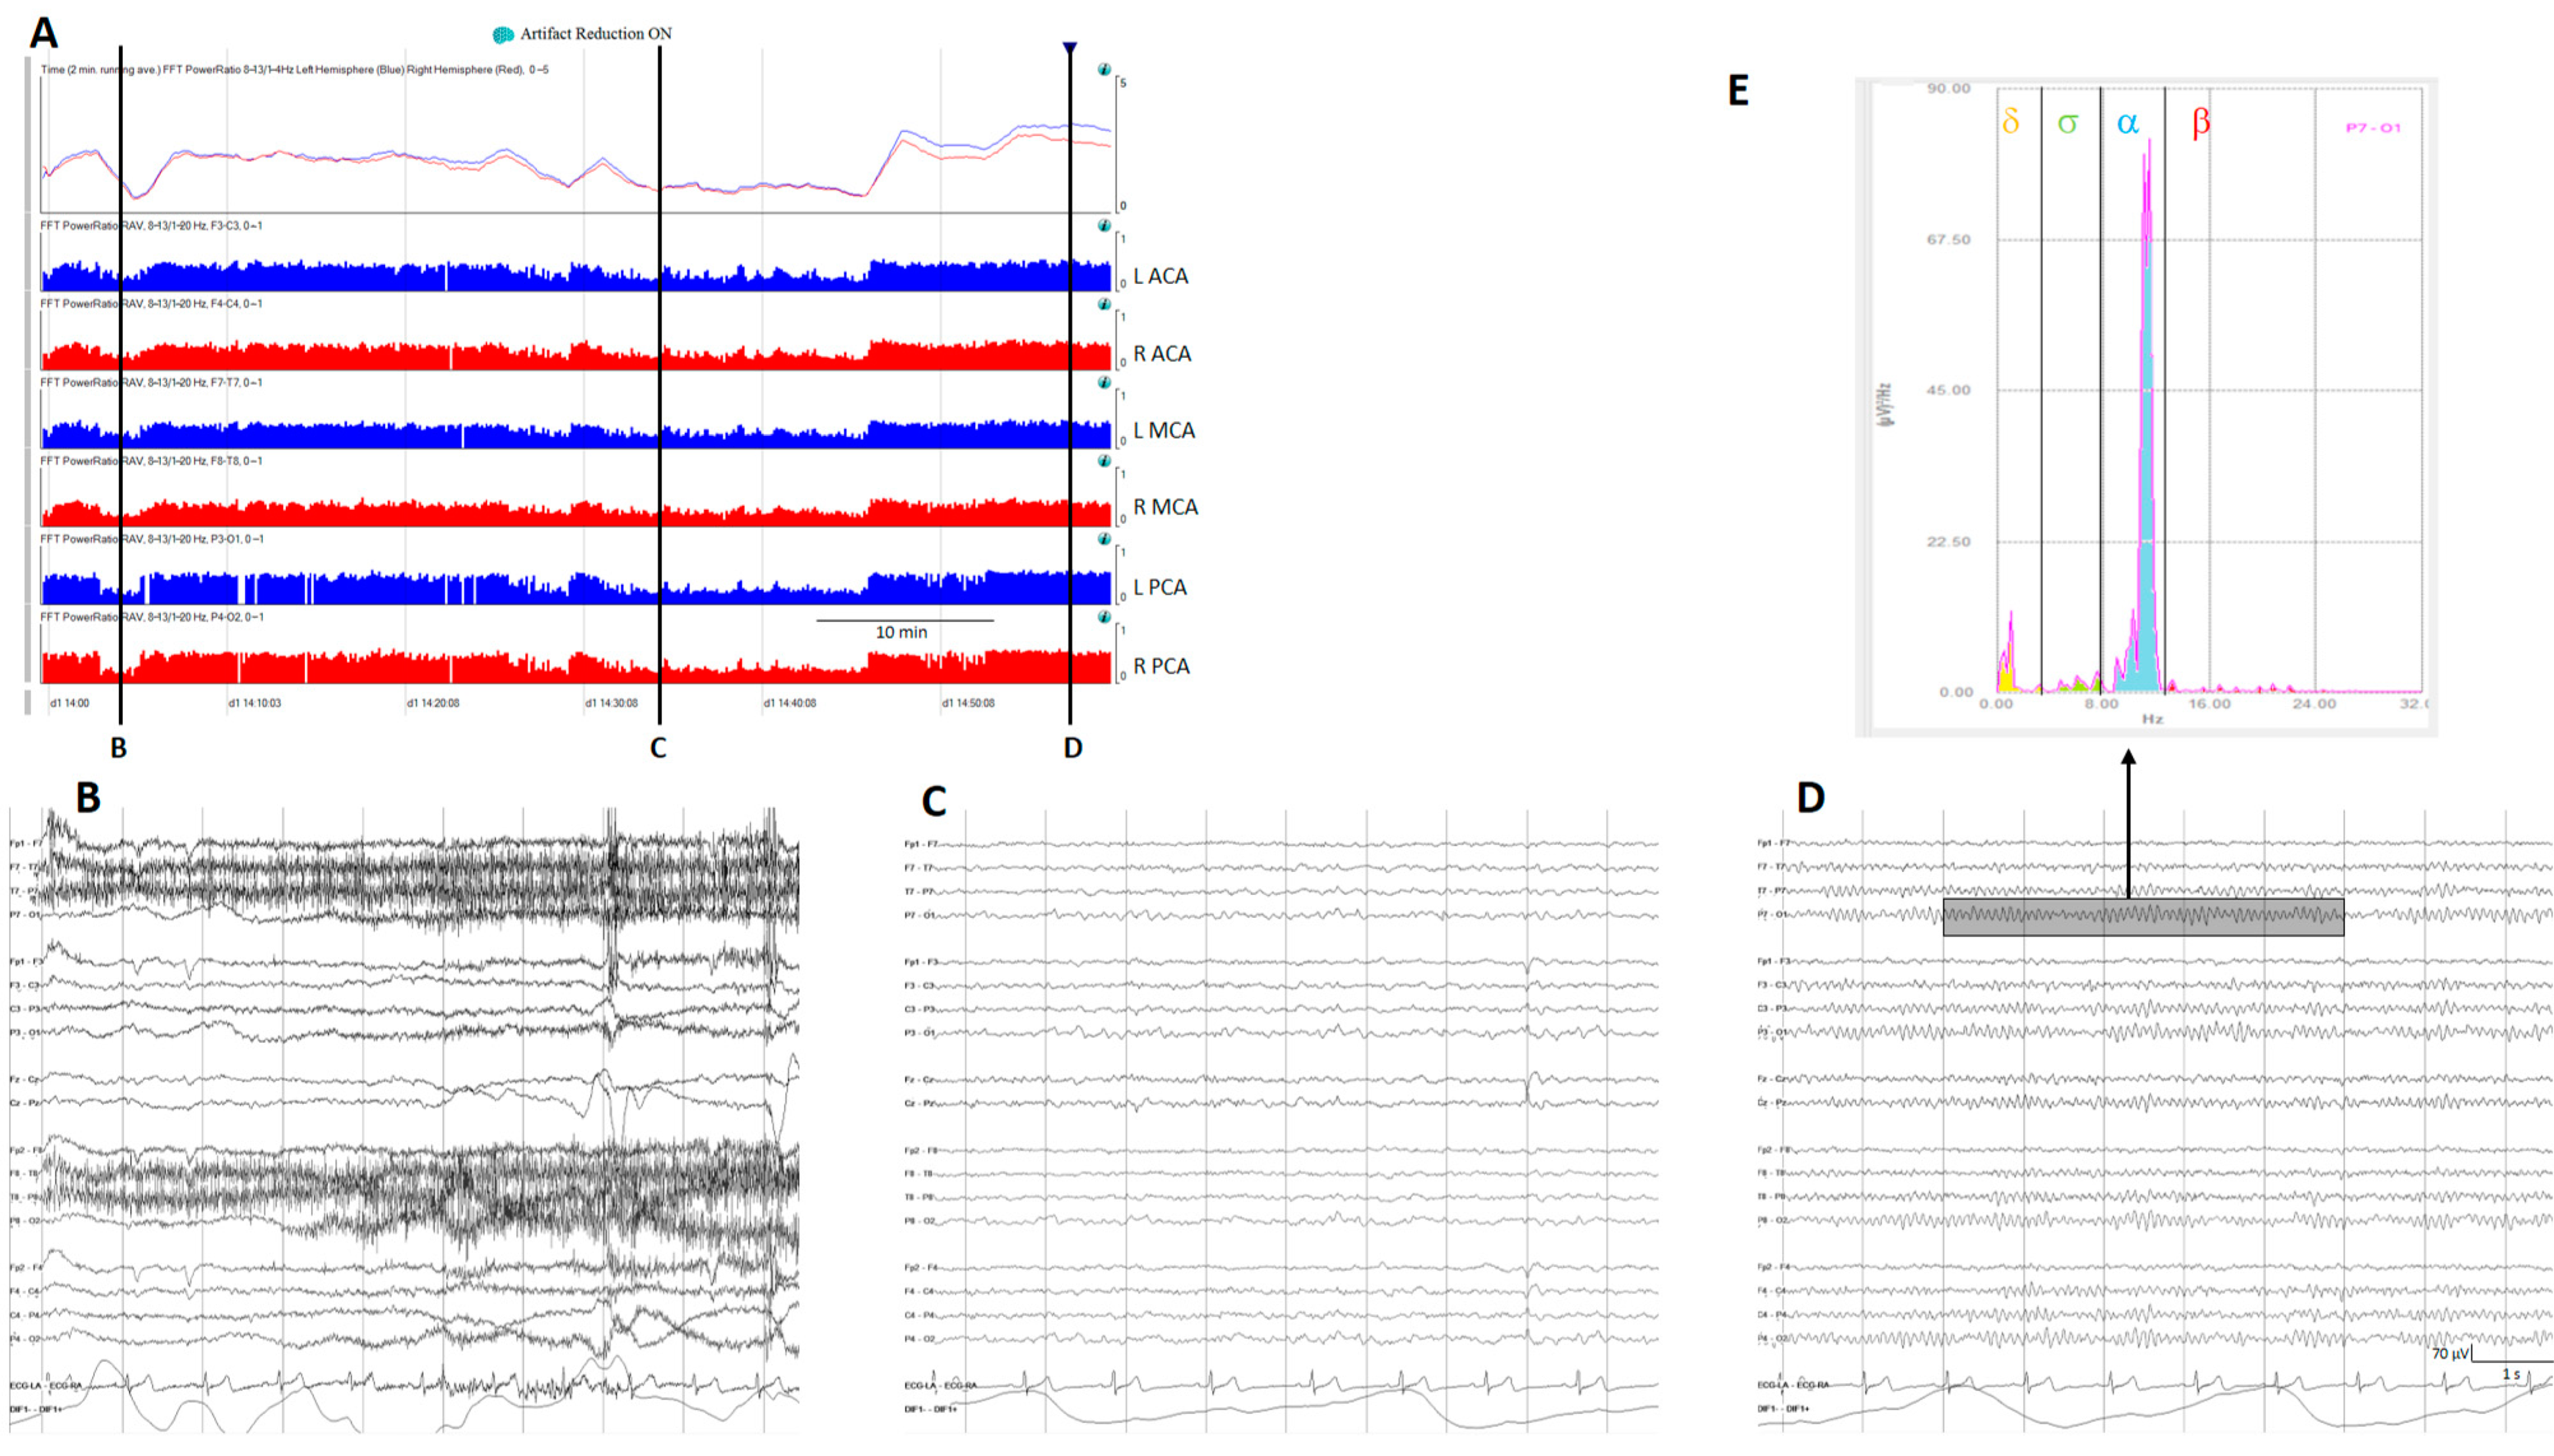

| ACA | MCA | PCA | ||

|---|---|---|---|---|

| Vespa et al., 1997 [26] | L | F3-T3 | T3-P3 | P3-O1 |

| R | F4-T4 | T4-P4 | P4-O2 | |

| Muniz et al., 2018 [89]; Rosenthal et al., 2018 [85]; Balança et al., 2018 [88] | L | F3-C3 | C3-T3 | P3-O1 |

| R | F4-C4 | C4-T4 | P4-O2 | |

| Zheng et al., 2022 [87] | L | Fp1-F7, Fp1-F3 | F7-T3, T3-T5, F3-C3, C3-P3 | T5-O1, P3-O1 |

| R | Fp2-F8, Fp2-F4 | F8-T4, T4-T6, F4-C4, C4-P4 | T6-O2, P4-O2 |